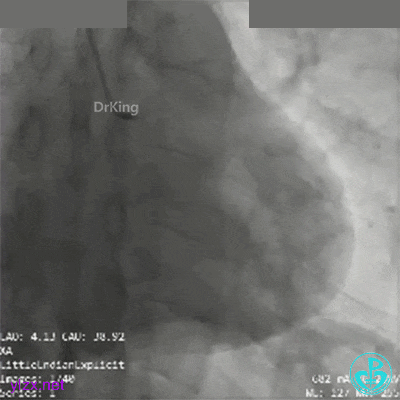

冠脉造影

RCA第一转折50%狭窄,第二转折前100%闭塞。